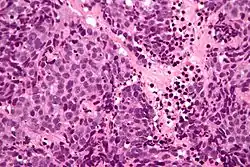

Micrograph of a sinonasal undifferentiated carcinoma. H&E stain.